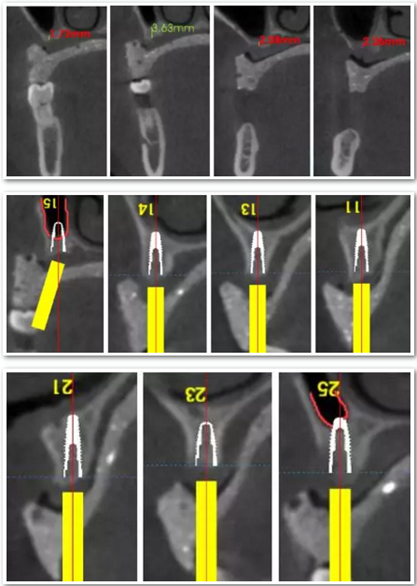

患者骨高度嚴(yán)重不足,尤其是后牙區(qū),骨高度基本都只有2mm。按常規(guī)傾斜植入的方式也不可行,因此選擇在5號(hào)位通過(guò)內(nèi)提升方式植入植體。

手術(shù)時(shí),帶上導(dǎo)板,逐級(jí)備孔,在15和25的位置需要進(jìn)行內(nèi)提升,因此對(duì)于備孔深度的把控尤為重要,導(dǎo)板的作用得到了重大發(fā)揮。